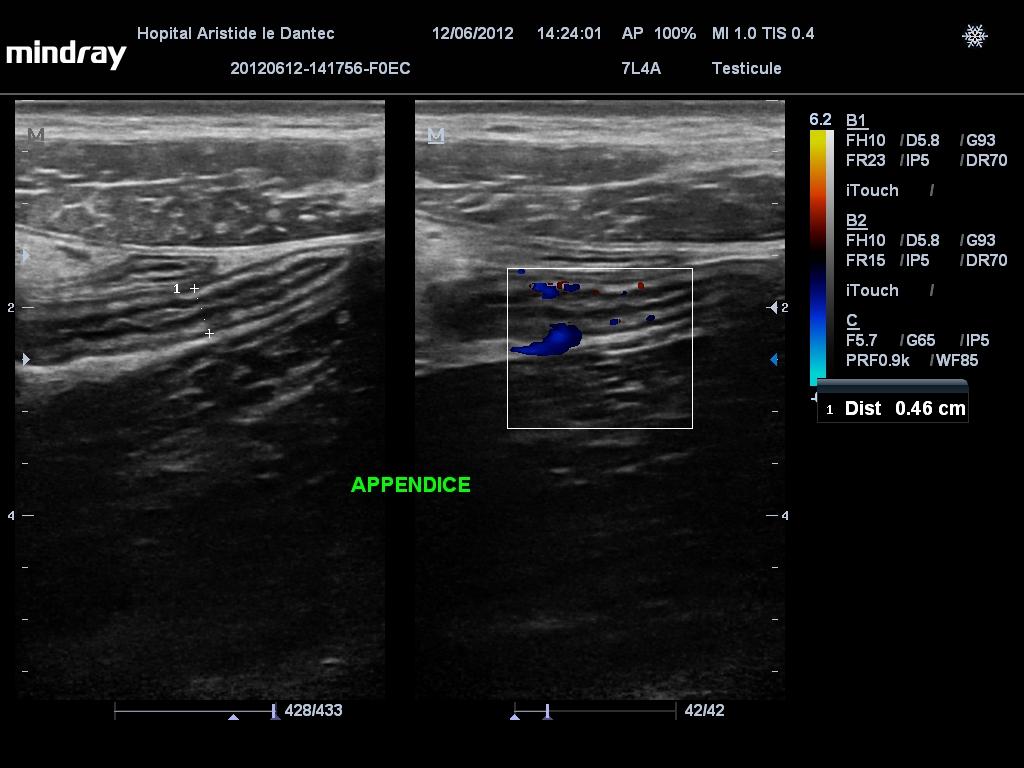

Ces Imagerie Medicale Ucad Douleur Fosse Iliaque Droite

Douleurs Abdominales Explorees Par Echographie Au Decours De La Consultation Ou La Naissance De L Echoscopie Fmc Hge